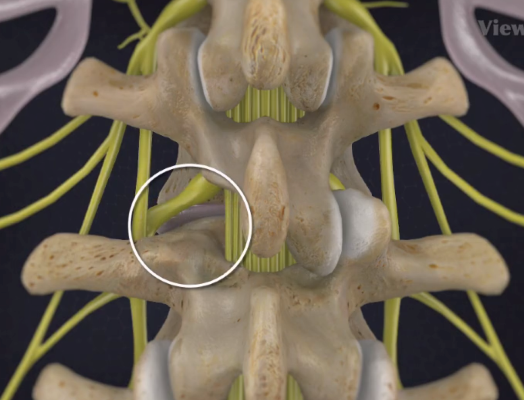

Pronunţîndu-se asupra tratamentului chirurgical anterior oferit pacientului, dr Bodiu a menţionat că, spre regret, acesta a fost operat prin metode tradiţionale şi nu a resimţit o ameliorare substanţială. Cazul dat se include perfect în noţiunea de ”sindrom de eşec al chirurgiei lombare”. Acesta defineşte situaţia cînd un pacient este operat la coloana vertebrală, dar continuă să aibă simptome persistente şi în perioada postoperatorie.

Astfel, în urma unui număr mare de investigaţii suplimentare, a fost luată decizia de a folosi un abord chirurgical numit ”fuziune intervertebrală transforaminală”. Tehnica dată este mai complicată şi mai solicitantă faţă de dotarea tehnică a blocului de operaţii şi a abilităţilor echipei chirurgicale, însă oferă un şir de avantaje pentru pacient.

Deoarece pacientul a fost operat anterior de 2 ori, utilizarea aceluiaşi coridor chirurgical tradiţional putea fi însoţită de un risc mare de leziuni a nervilor şi vaselor în canalul spinal. De aceea, a fost aleasă o cale mai puţin utilizată în practica cotidiană, dar care a fost cea mai raţională pentru pacientul dat, aşa-numitul abord paramedian transmuscular sau abordul prin spaţiul Wiltse.